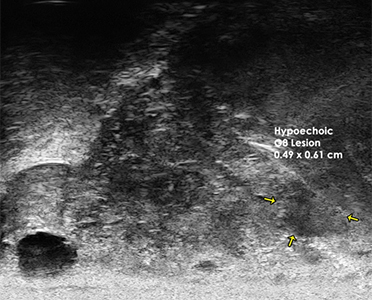

The 29 MHz ExactVuTM system facilities resolution down to 100 microns – and enables

detailed visualization in real-time of the prostate anatomy and characterization of

the prostatic tissue.

The following are select cases that are routinely derived from the ExactVuTM

micro-ultrasound platform and verified with pathological results.